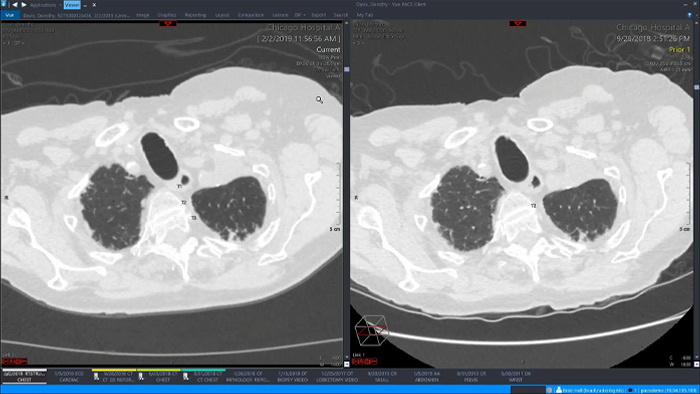

Let’s take a look at some of the immediate benefits of a unified approach. A single, unified workspace for radiology would incorporate advanced 3D post-processing and image distribution capabilities, opened in an additional viewer tab for ease.

A unified workspace would mean that users can easily launch the relevant analysis tools from among the 70+ advanced applications available across multiple clinical domains. Artificial Intelligence can play a role by automating tasks and workflows, predicting usage patterns.

An all-in-one workspace, fully integrated with the enterprise imaging platform and embedded in the diagnostic viewer, offers simple, efficient access to all needed tools across clinical domains. One-click access to advanced visualisation tools – such as virtual colonoscopy, 3D processing, and spectral imaging – allows for efficient interpretation and supports diagnostic confidence.

Offers advanced visualisation with a robust set of tools for AI-assisted quantitative assessment and automatic results generation.